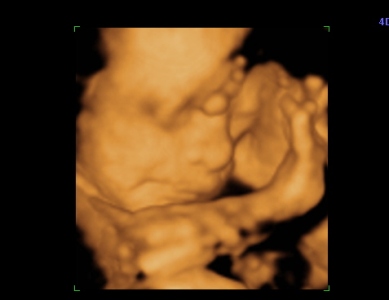

Na hát megvolt a 4D. Jó sokat időztünk ott, Mártika annyira kedves volt kaptam csokit ,colát, sétáltam mert a drágánk a feje előtt tartotta a két kezet plusz az egyik lábfejét, és belebújva a méhlepénybe. Szóval alig se nagyon látszott valami kb 1órát időztünk. HÁt ezért szeretek én a Genesisbe menni mert annyira lelkiismeretesek.

Hoztam pár képet

pofi

Kép

keze

tuti lányos